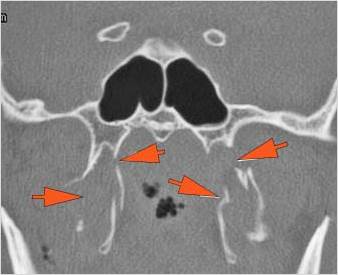

The alveolar ridge, premaxilla, and/or the palatine process of the maxillary bones on either side are fractured. [Yes/No]

The hard palate is fractured. [Yes/No]

The pterygoid processes of the sphenoid bone are fractured. [Yes/No]